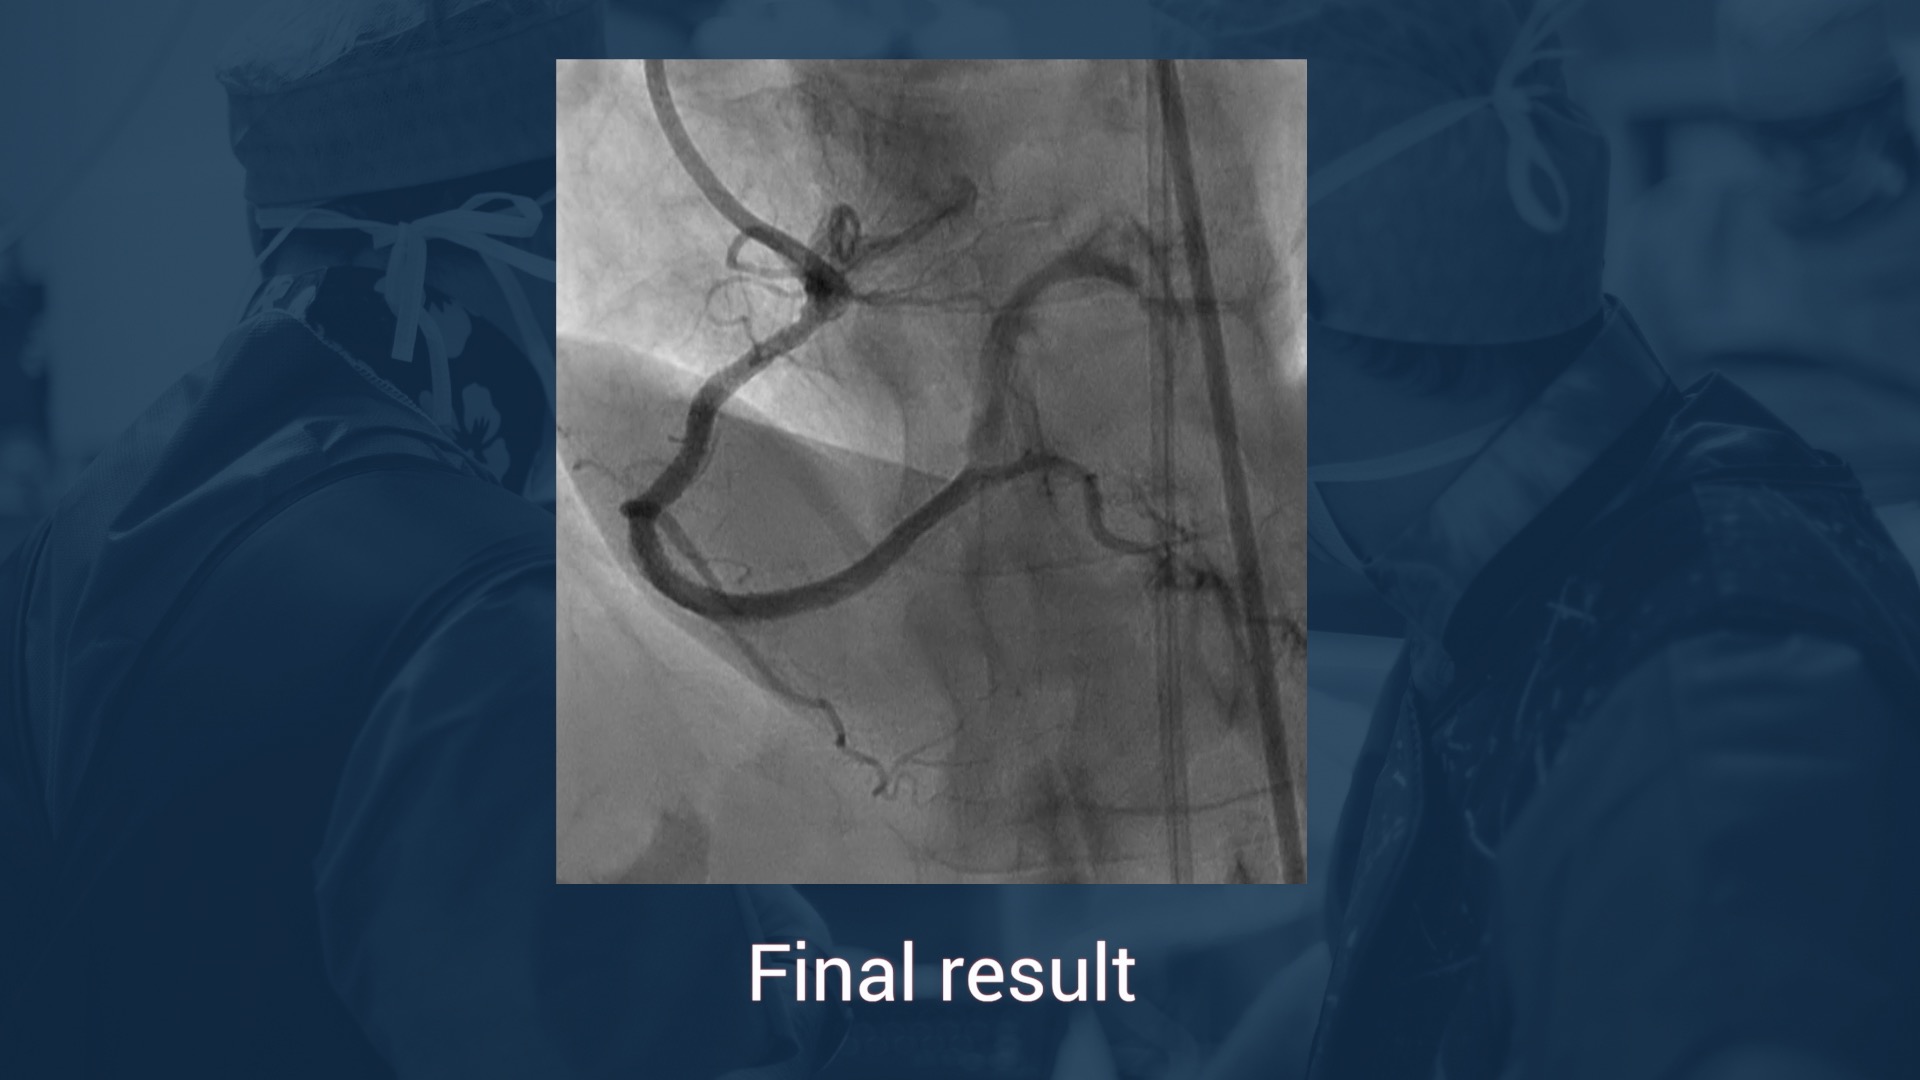

• Coro:  chronic total coronary occlusion of the right coronary artery,significant stenosis of the PDA, significant stenosis of the distal left main trunk ant of the proximal LAD